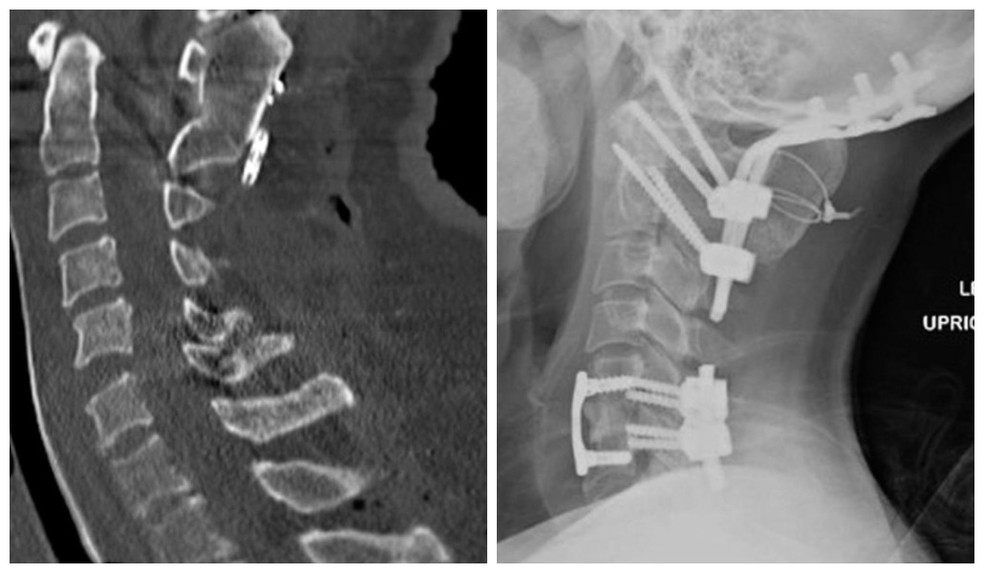

Traumas raros, mas não inéditos - Um caso de "dissociação craniocervical" foi relatado em artigo de 2021 no "International Journal of Surgery": um paciente de 25 anos que sofreu a dissociação após um acidente de carro. O paciente apresentava perda de consciência, paralisia e dificuldade para respirar.

Ele foi submetido a uma cirurgia para restaurar a estabilidade da coluna cervical e remover um coágulo de sangue do cérebro. O paciente se recuperou completamente da lesão e foi capaz de retornar à sua vida normal.

Veja abaixo as imagens do antes e depois da lesão:

(Crédito: International Journal of Spine Surgery/Divulgação)